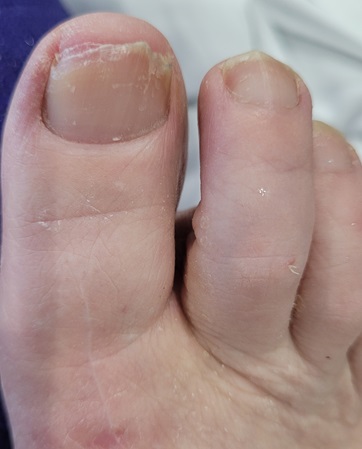

This issue will not apply to all surgeries either. It depends how long your post-op period is AND the degree of immobility required. For example, I’ve had both ankles fused. Same post-op period in both cases. However, with the left ankle I could drive four weeks earlier than with the right ankle and that four weeks, plus an additional, unrelated, hospitalisation, were enough to make what was, in my case, a major difference.

When I had the left ankle done in 2023, by the time I was in a moonboot and on crutches I could drive to the gym and do the weighted back exercises I needed to do to maintain my posterior chain strength. With the right ankle, obviously I couldn’t drive for an additional month. Then, two weeks after I could drive, I was back in hospital for a nasal/sinus infection. Essentially immobile again.